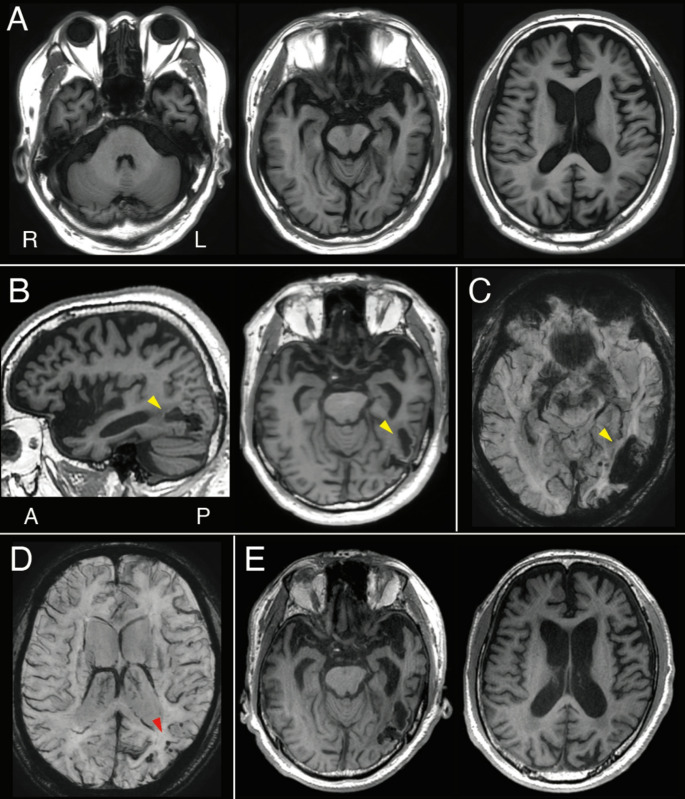

脑淀粉样血管病引起的左颞下出血,类似语义性痴呆。

Left inferior temporal hemorrhage due to cerebral amyloid angiopathy mimicking semantic dementia.